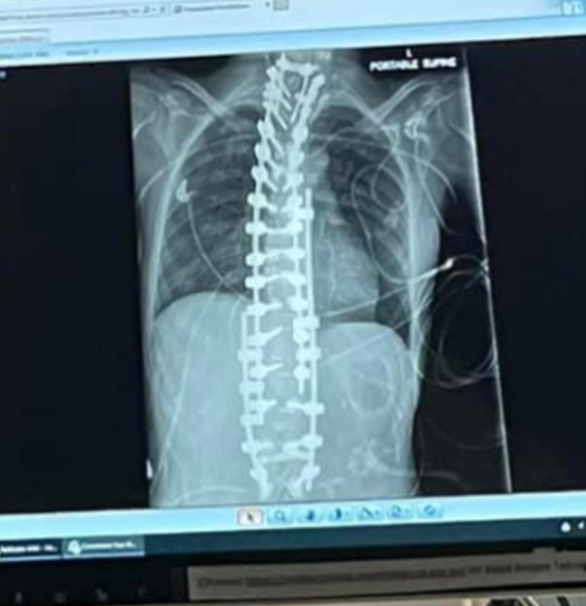

Tragically, the horrors of her condition don't stop there. Steroids, a major part of her treatment, came with devastating side effects, including severe osteoporosis.

Her bones became so fragile that she fractured her spine in several places and even suffered a broken sternum after dozing off on a hospital railing for just a few minutes.

Doctors told her there was nothing more they could do. Her spine couldn't be fixed because her bones were too weak to support any kind of surgery.

An x-ray of Annaliese "Annie" Holland's spine, from a post dated September 27, 2023 | Source: Instagram/annaliese_holland

But Annie wasn't ready to give up. With unshakable determination, she scoured the internet and found a doctor who specialized in operating on elderly women with osteoporosis.

It was a last-ditch gamble, but they had no choice, as her spinal cord was just one fracture away from snapping completely. She endured a brutal 13-hour surgery, fell into a coma for five days, and spent two months recovering in the hospital.

In the end, it was worthwhile, as she got to have a straight back. But the steroids took yet another cruel toll. They caused necrosis, cutting off blood flow to her bones.